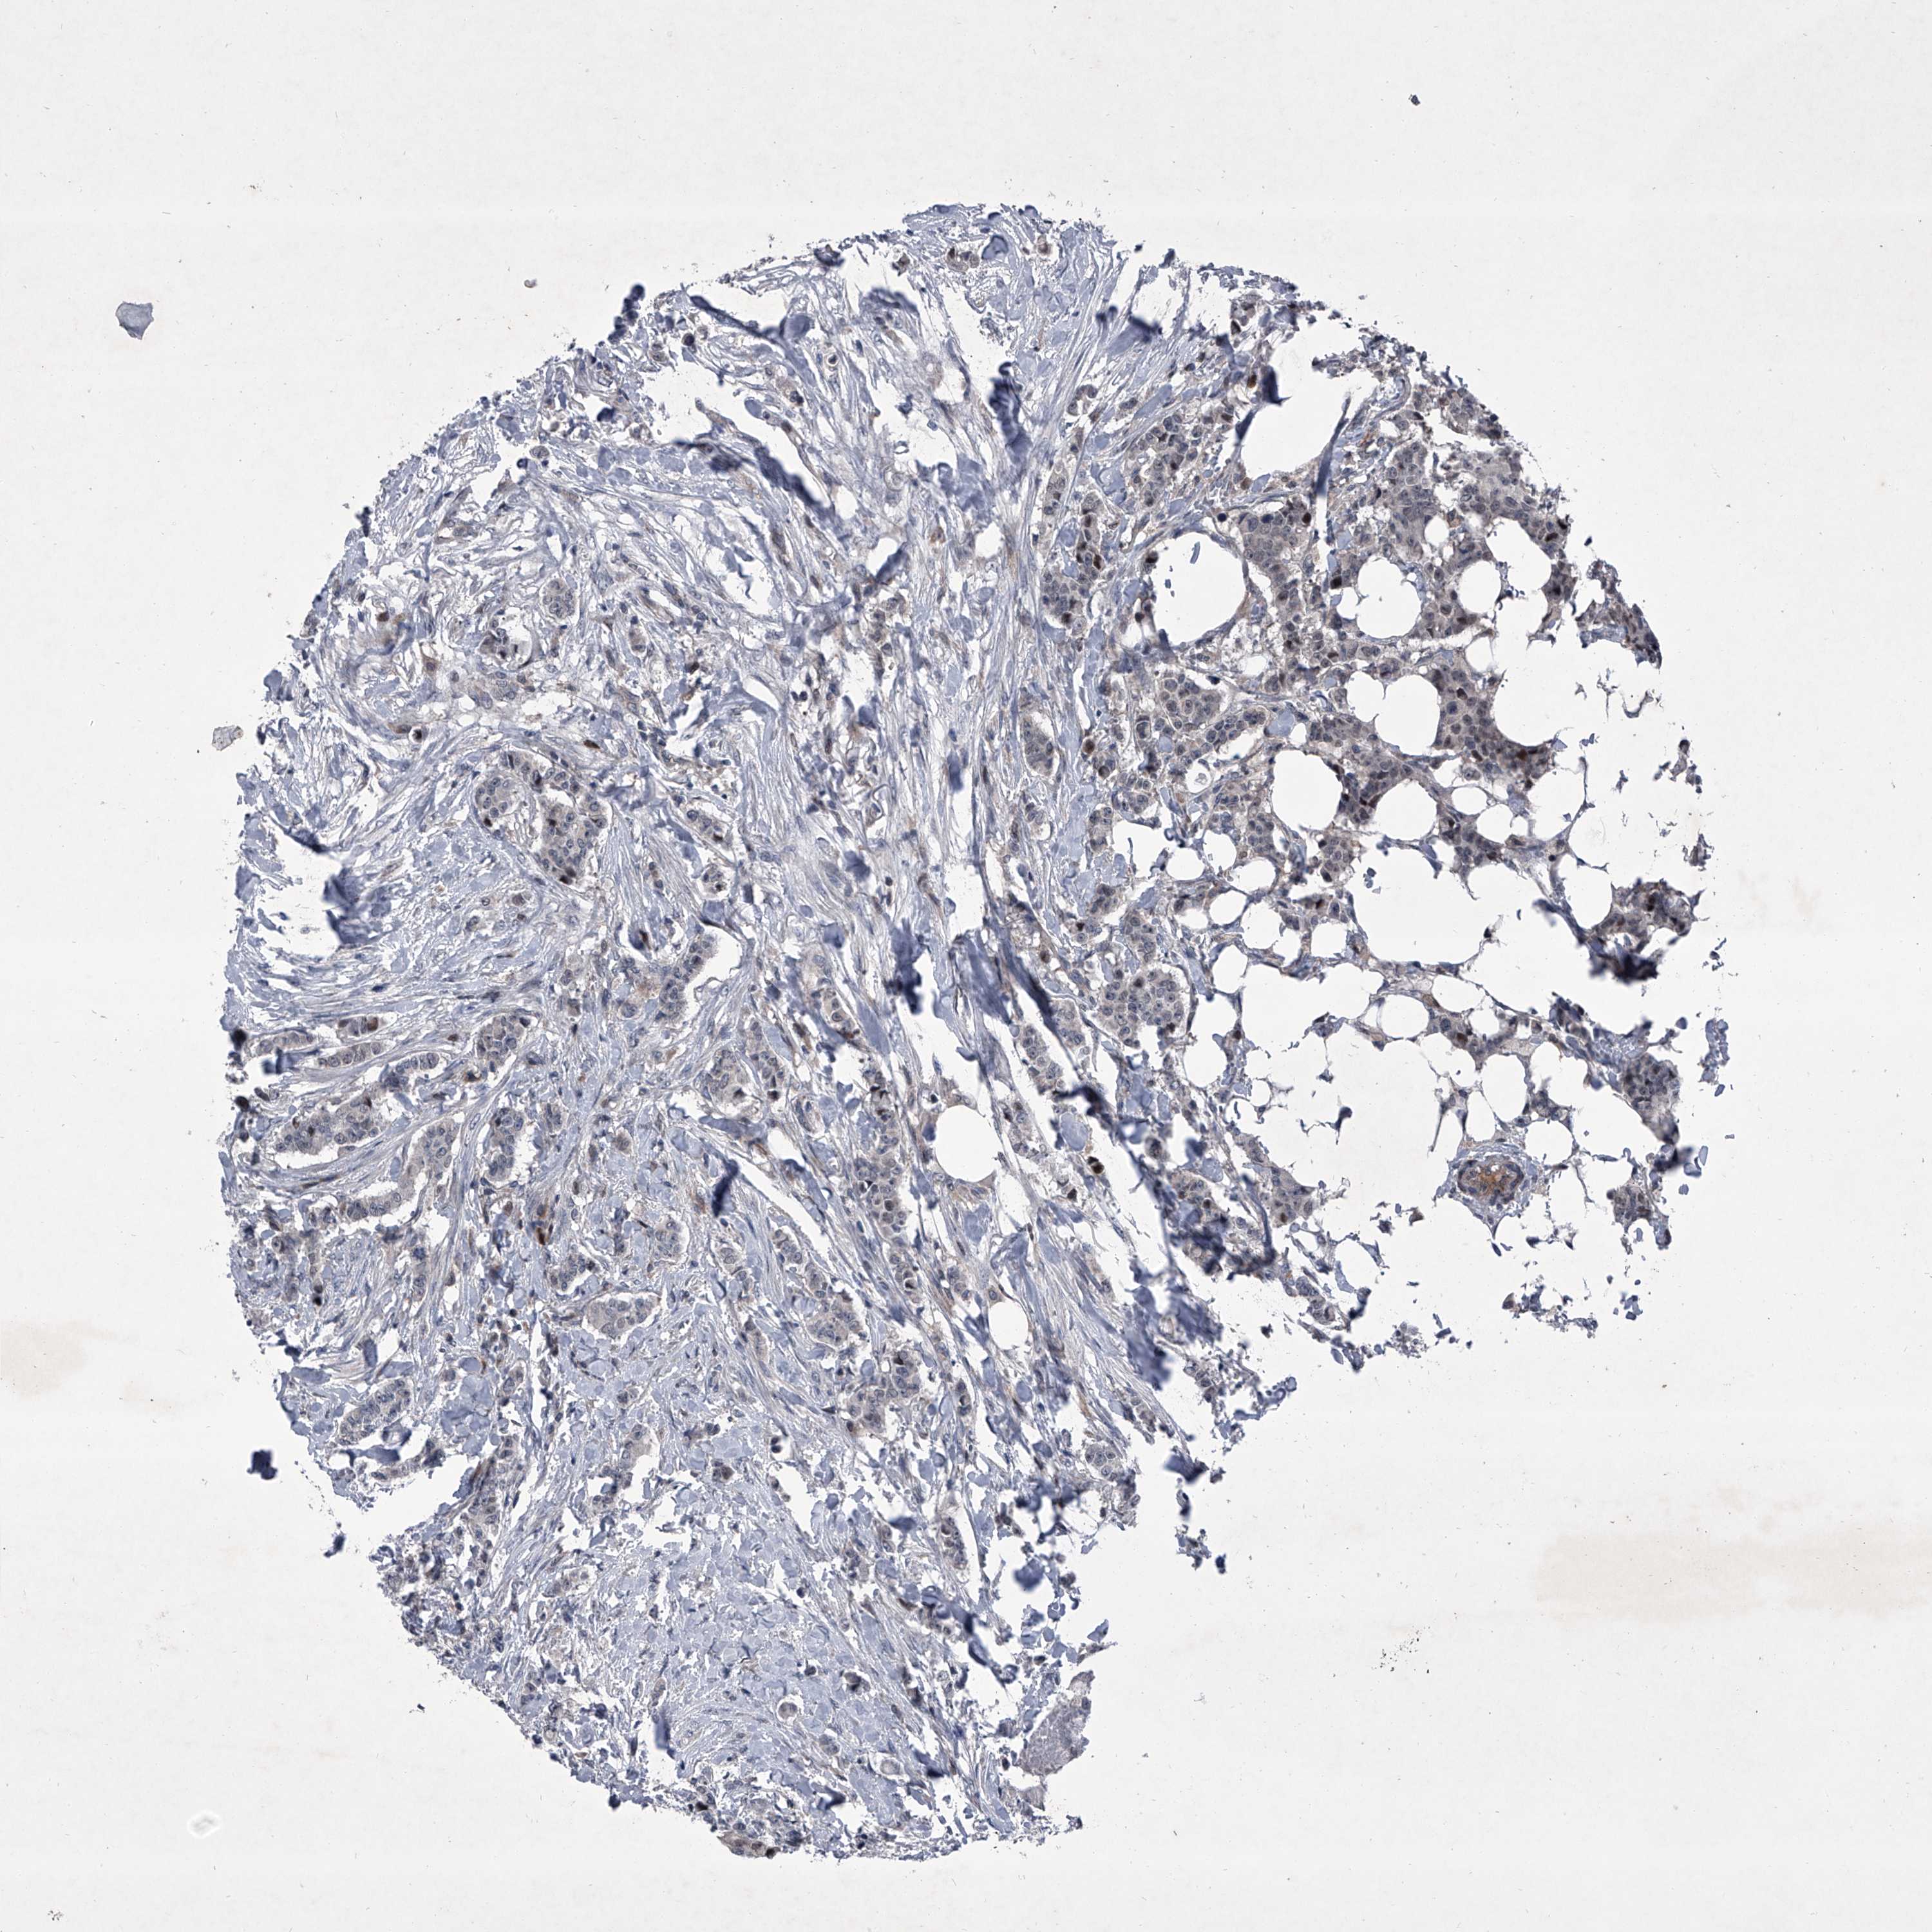

BRCA TCGA BRCA VALIDATION PROTEIN EXPRESSION

ANTIBODIES

AND

VALIDATION